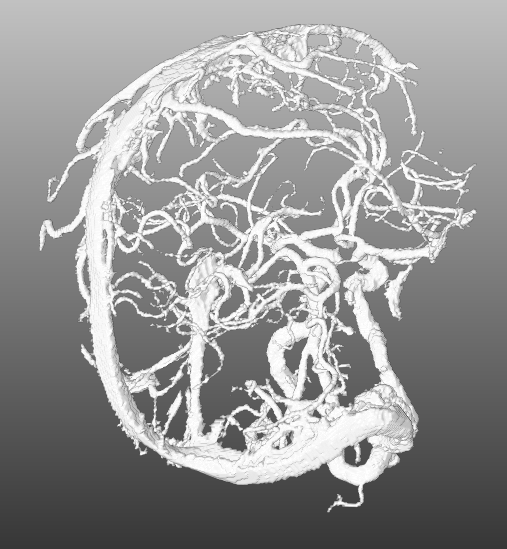

4.2 Modelling

For the interactive part of our work, the segmentation must be modeles as geometric representation e.g. as graph of centerlines and lumen radii. First, as tiny gaps may occur in the segmentation, closing is applied, followed by the Distance-Transform-Skeletonization algorithm (short, DTF-Skeletonization) (Selle, 2000), which returns not only the skeleton itself but also a surface model of the vascular structures. Examples trees are shown in Fig. 3, Fig. 5, Fig. 5 and Fig. 6(a). Once the model is available, the information required of the interactive masking (geodesic distances) is computed in Fig. 2(k). As the processing consists primarily of searching pathways on the skeleton representation, the step is called “Graph Search”. In Sec. 4.2.1 we present the generic concept of pathway searches on vessel trees, from which it is possible to derive applications. Exemplarily, we present two applications consequently following from the formal concept introduction, namely the interactive path search in Sec. 4.2.3 and the interactive suppression of veins in Sec. 4.2.2.

5.1 Segmentation and Modelling

For quantitative evaluation of the segmentation no ground-truth data was available. The annotation of such data is very time consuming but will be part of future work. Consequently the modelling, in particular the DTF-Skeletonization, cannot be quantitatively evaluated as well. Qualitatively, however, small modelling artifacts in forms of artificial loops and bridges may appear in some cases in the surface model if vessel section are very close to or touching each other. Under this link we published several videos to demonstrate the interaction with the vessel tree using the vein suppression and the path planning.